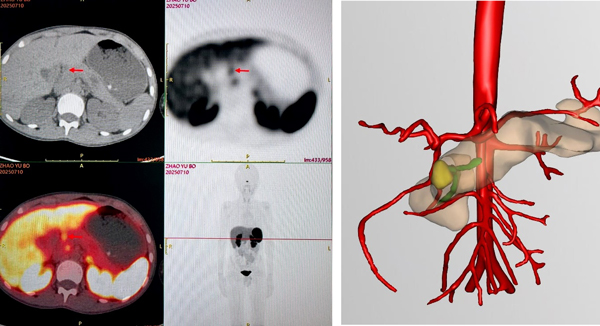

术前影像检查显示胰头前方高摄取病灶,

三维影像重建提示肿瘤紧邻主胰管